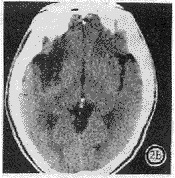

图2 左偏瘫5h,CT平扫显示右侧脑岛带区灰质密度降低与白质一致(脑岛带征)(a),33h后复查,脑岛带区呈明显低密度影(b)。

幕上209例,大脑中动脉供血区197例,大脑前动脉供血区8例,大脑后动脉供血区4例,右小脑半球1例。CT征象阴性40例,致密动脉征表现为平扫CT图像上脑动脉密度增高,超过脑皮质密度,低于钙化密度。豆状核征表现为豆状核轮廓模糊,密度与脑白质一致或稍低(图1)。脑岛带征表现为脑岛带区灰白质界面模糊,灰白质密度一致(图2)。低密度灶分腔隙性(<1cm为小腔梗,1~1.5cm大腔梗)和片状(>1.5cm)。占位征表现为邻近脑室、脑池、脑沟变小(图3)。皮质征表现为皮质局限性密度减低,与脑白质密度一致(图4)。各征象在不同时间出现率见表1,敏感性等指标测定结果见表2。